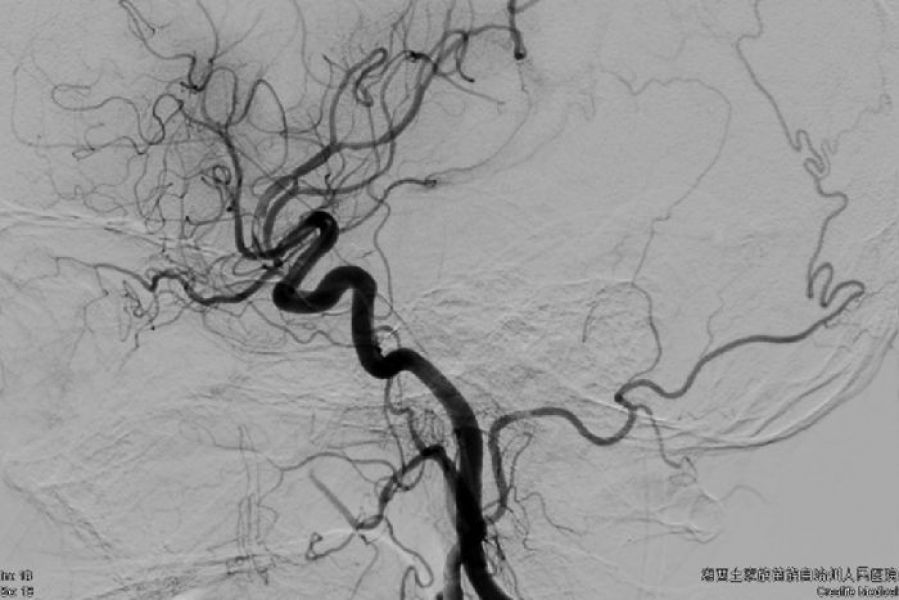

由于当时医院两台DSA都有手术,时间就是大脑,每延迟一分钟开通血管,大脑细胞就有近200万个细胞死亡。经过积极协商,其他科室也很理解的将常规介入手术后延,迅速空出一台DSA机,在16:35 将患者安全送入DSA室进行急诊介入治疗。田勇副主任医师、梁承财主治医师和介入科护士及技师熟练的配合,有条不紊而又迅速完成消毒,铺单,股动脉穿刺,脑血管造影,明确血栓堵塞左侧大脑中动脉主干,患者左侧大脑前动脉A1段先天性缺如,右侧大脑前动脉A1供应双侧大脑前A2及以远血供,造影结果再次确认患者非常适合支架动脉内取栓。经过两次动脉支架植入血栓-静置-回抽拉栓,取出一块红色混合血栓,有部分血栓残留在大脑中动脉分支起始部,患者闭塞血管前向血流完全恢复正常,成功将患者从死神手中挽救出来。术后第二天,患者清醒,手脚可勉强抬起,肌力恢复到3级,术后第三天,患者可自行行走,右侧肢体肌力恢复到4级。目前患者已经康复无残疾出院。

术后